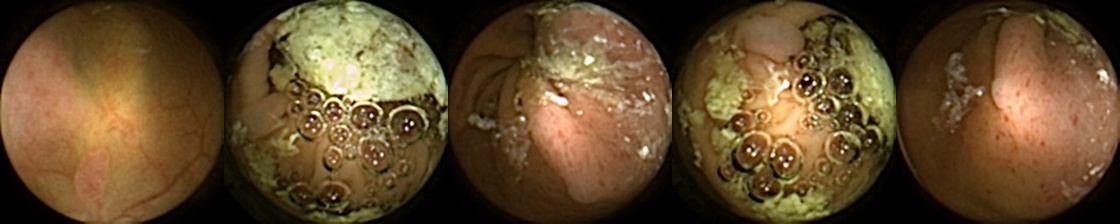

We can additionally consider the confusion matrices from the best MIV model associated with (a) the pretrained ConvNext and (b) SimCLR pretraining using the ConvNext backbone in Figure 5. We note that using SimCLR achieves a better ratio of False Negatives (70) to False Positives (38) as compared to pretrained ConvNext, which has 109 False Negatives and 23 False Positives.

Refer to caption

Figure 5: Confusion matrices from the best MIV model associated with (left) the pretrained ConvNext, and (right) SimCLR pretraining using the ConvNext backbone